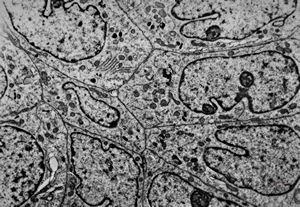

F,49y. | purulent meningitis- meningococcal v.s.

F,49y. | purulent meningitis- meningococcal v.s.

F,49y. | purulent meningitis- meningococcal v.s.